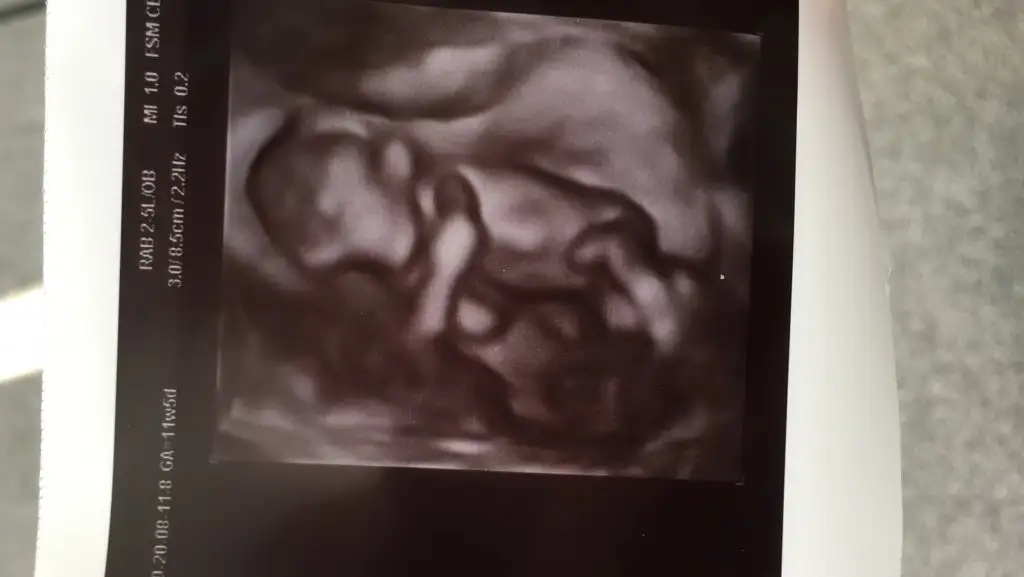

Maşallah sağlıkla ilerleyin hep. Usg 4 boyutlu mu. Çok güzel görünüyorBen de doktora gittim bugün ilk girdiğimde uyuyordu doktor o kadar salladı karnımı asla uyanmadı derin uykudaydı tostosum yüzü bize dönük uyuyordu bacaklarını uzatmıştı haftasıyla uyumlu dedi tam günü çıktı 11+5 günlük ikili için ense kalınlığı alcak kadın alamadı uyanmayınca git biraz çikolata ye gez dolaş, ikili test için kan ver dedi. Yarım saat sonra gittim partiliyordu bizimki içerdeilk defa çikolata yedim bir de demiştir ki hmm bu nasıl bir lezzet kıza benzettim ama bir ay sonra kesinleşir dedi. İkilinin sonucu 4 gün sonra çıkarmış ense kalınlığı 1.9 çıktı iyi gözüküyor dedi. Eki Görüntüle 2674088

Ben de doktora gittim bugün ilk girdiğimde uyuyordu doktor o kadar salladı karnımı asla uyanmadı derin uykudaydı tostosum yüzü bize dönük uyuyordu bacaklarını uzatmıştı haftasıyla uyumlu dedi tam günü çıktı 11+5 günlük ikili için ense kalınlığı alcak kadın alamadı uyanmayınca git biraz çikolata ye gez dolaş, ikili test için kan ver dedi. Yarım saat sonra gittim partiliyordu bizimki içerdeilk defa çikolata yedim bir de demiştir ki hmm bu nasıl bir lezzet kıza benzettim ama bir ay sonra kesinleşir dedi. İkilinin sonucu 4 gün sonra çıkarmış ense kalınlığı 1.9 çıktı iyi gözüküyor dedi. Eki Görüntüle 2674088